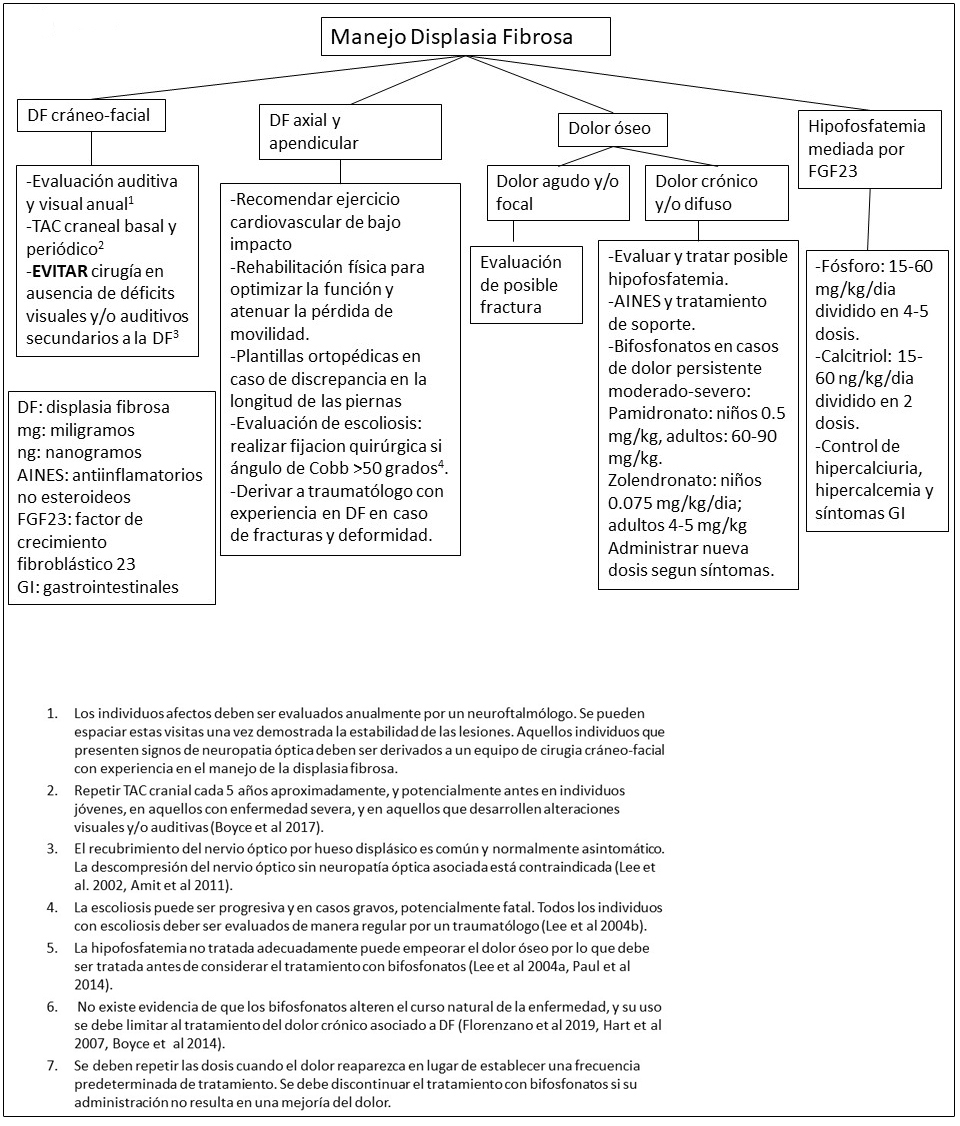

El dolor óseo es una complicación muy común de la DF. Aunque el dolor pueda manifestarse a cualquier edad, lo más típico es que no esté presente durante la infancia, aparezca durante la adolescencia, y progrese durante la vida adulta (Kelly et al 2008).

La producción aumentada de la hormona factor de crecimiento fibroblástico 23 (FGF23) en áreas de DF puede resultar en una tubulopatía renal con pérdidas urinarias de fosfato (Collins et al 2001). No obstante, no es frecuente que se detecte hipofosfatemia franca en pacientes con DF dado que la mayor parte del FGF23 producido, es degradado en el tejido displásico (Bhattacharyya et al 2012). El grado de sobreproducción de FGF23 en pacientes con DF suele correlacionarse con el grado de extensión de la enfermedad esquelética, por lo que los casos de hipofosfatemia franca sólo afecta a individuos con una afectación esquelética extensa (Rimunucci et al 2003).

Los individuos que presenten hipofosfatemia franca tiene un riesgo incrementado de padecer raquitismo, osteomalacia, fracturas y dolor óseo (Lee et al 2004a).

Tratamiento de las manifestaciones

Figura 11. Manejo clínico recomendado para individuos con Displasia Fibrosa